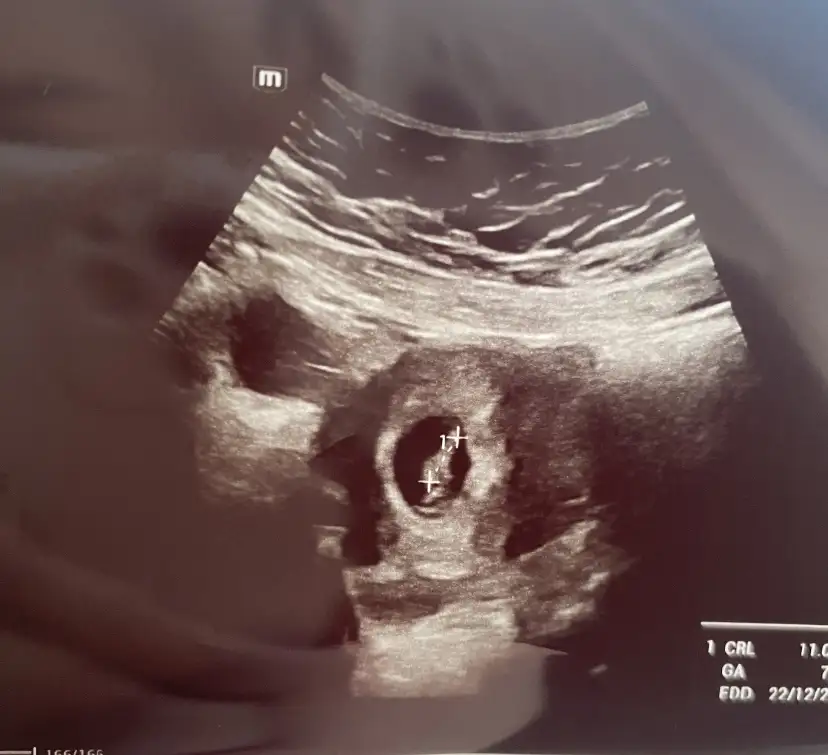

Ben iş yerinden 2 kişiye söyledim biri şefimdi izin alırken zorluk olmasın istedim. Diğeri yakın olduğum biri. Şey dedi ben zaten anlamıştım sürekli baygınlık geçiriyodunUyku konusunda ben de öyleyim. Öğle yemeğinden sonra performansım düşüyor. Ben bi'de finanstayım ödüm kopuyor yanlış ödeme falan yaparım diyeBir de ben daha ofiste kimseye söylemedim herkes hastaneye git halsizsin bu ara diyor bakalım şu ayı bi geçirelim de sonra söylicem artık